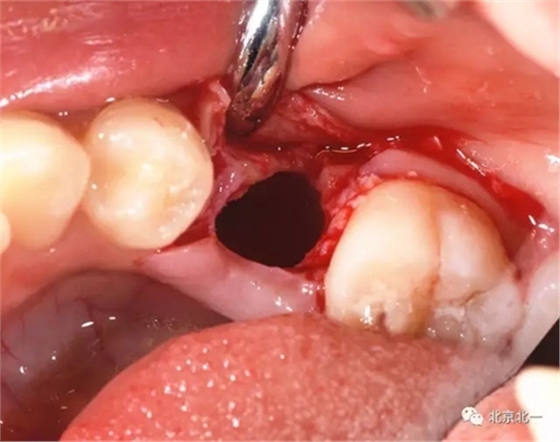

拔牙前臨床照片

術(shù)中有絲分裂

埋伏牙專用攪碎機攪碎牙齒